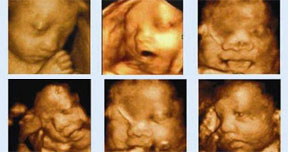

這段期間寶寶的皮下組織較飽滿,面部的表情也比較豐富,同時(shí)也會(huì)分娩做好準(zhǔn)備。